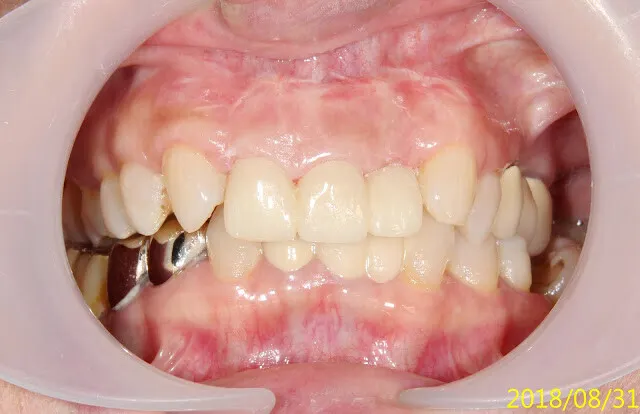

假牙材質4臨床案例---上門牙車禍+雕蠟模型